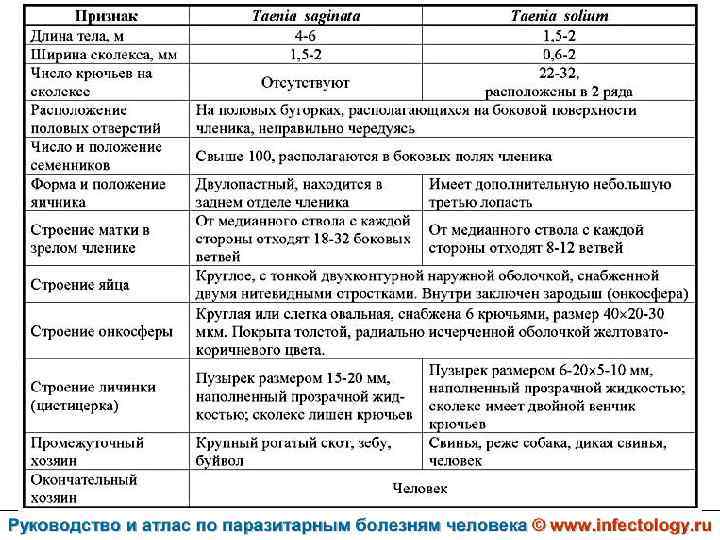

Тениаринхоз (шифр по МКБ 10 - B 68. 1) – антропонозный биогельминтоз с хроническим течением, характеризующийся преимущественно желудочно– кишечными расстройствами.

Тениоз (шифр по МКБ 10 - B 68. 0) – антропонозный биогельминтоз, одним из основных клинических проявлений которого является нарушение функций желудочно– кишечного тракта.